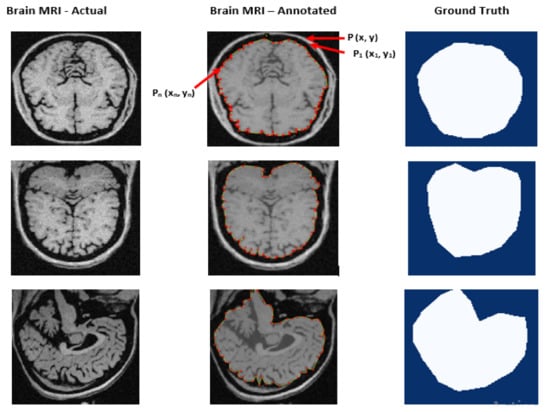

We employed two state-of-the-art image segmentation methods, viz., BET and BSE for generating baseline values of brain MR images to understand the effectiveness and precision of our experimented method. BET is a traditional method widely used for skull stripping. It segments the brain tissues from the non-brain tissues by using features such as intensity, shape, and contrast of brain MR images [53]. BSE is also a traditional method that uses several filters, edges, detection, and morphological operations to extract the surface of brain MR images [6]. We created ground truth (GT) by contouring the cerebrum area using polygonal labeling. Moreover, we segmented the same brain MR image using BET and BSE techniques. We treated selected brain MR images to remove noise because both baseline methods require noise-free images. BET utilizes a deformable model to segment the input MR image while using a non-linear smoothness technique for noise treatment. BSE combines edge detection and morphology-based techniques to segment the input MR image using an anisotropic diffusion technique for noise treatment. Contrary to this, the Mask–RCNN-based experimental method does not require noise treatment. Figure 4 depicts the output of baseline segmentation.

Figure 4. Generation of baseline segmentation results for Ground Truth and comparison of results.